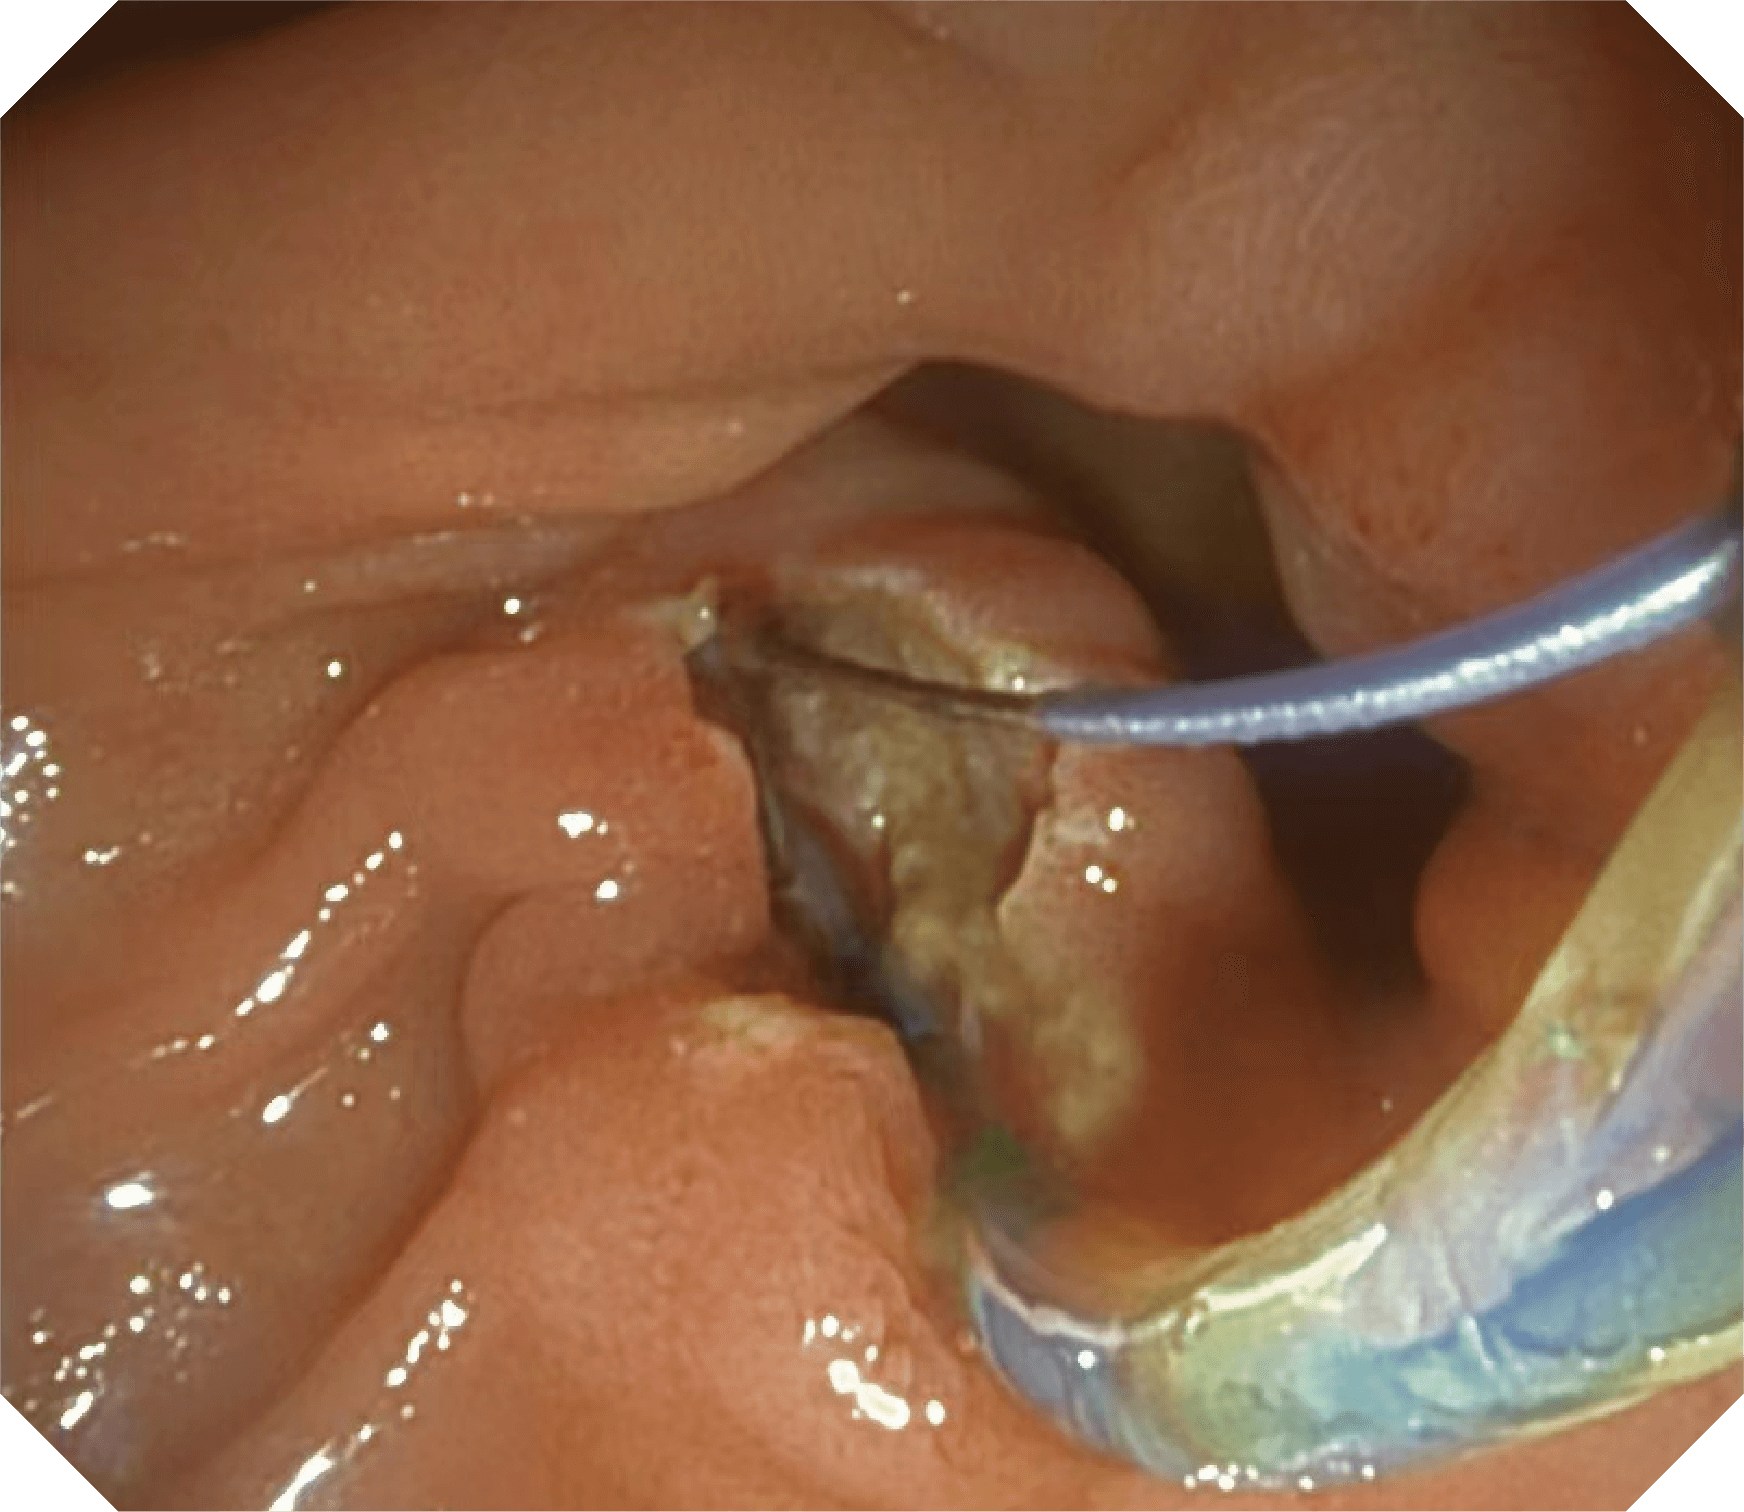

导丝机械锁紧功能

V槽设计提升导丝控制

优异的手术器械抬举性

当切开刀伸出视野外时,导向面引导其回归视野